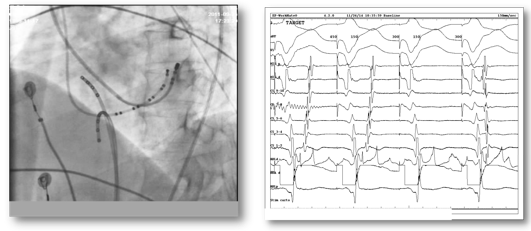

首先对导管插入部位(腹股沟、手臂、肩膀或颈部)的皮肤消毒,局麻药进行局部麻醉;然后用穿刺针穿刺静脉/动脉血管建立通道,电生理检查导管通过血管插入心腔;心脏电生理检查所用的电极导管是长而可弯的导管,能将电信号传入和传出心脏(图2)。

图2. X影像下心脏内电生理导管位置(左图)及电极记录到的心电信号(右图)

电极导管记录心脏不同部位的电活动,也可发放微弱的电刺激来刺激心脏,以诱发心律失常,明确心动过速类型诊断;然后医生通过导管找到心脏异常电活动的确切部位(此过程称为“标测”),再通过射频消融仪发送射频电流消融治疗,从而根治心动过速(图3)。